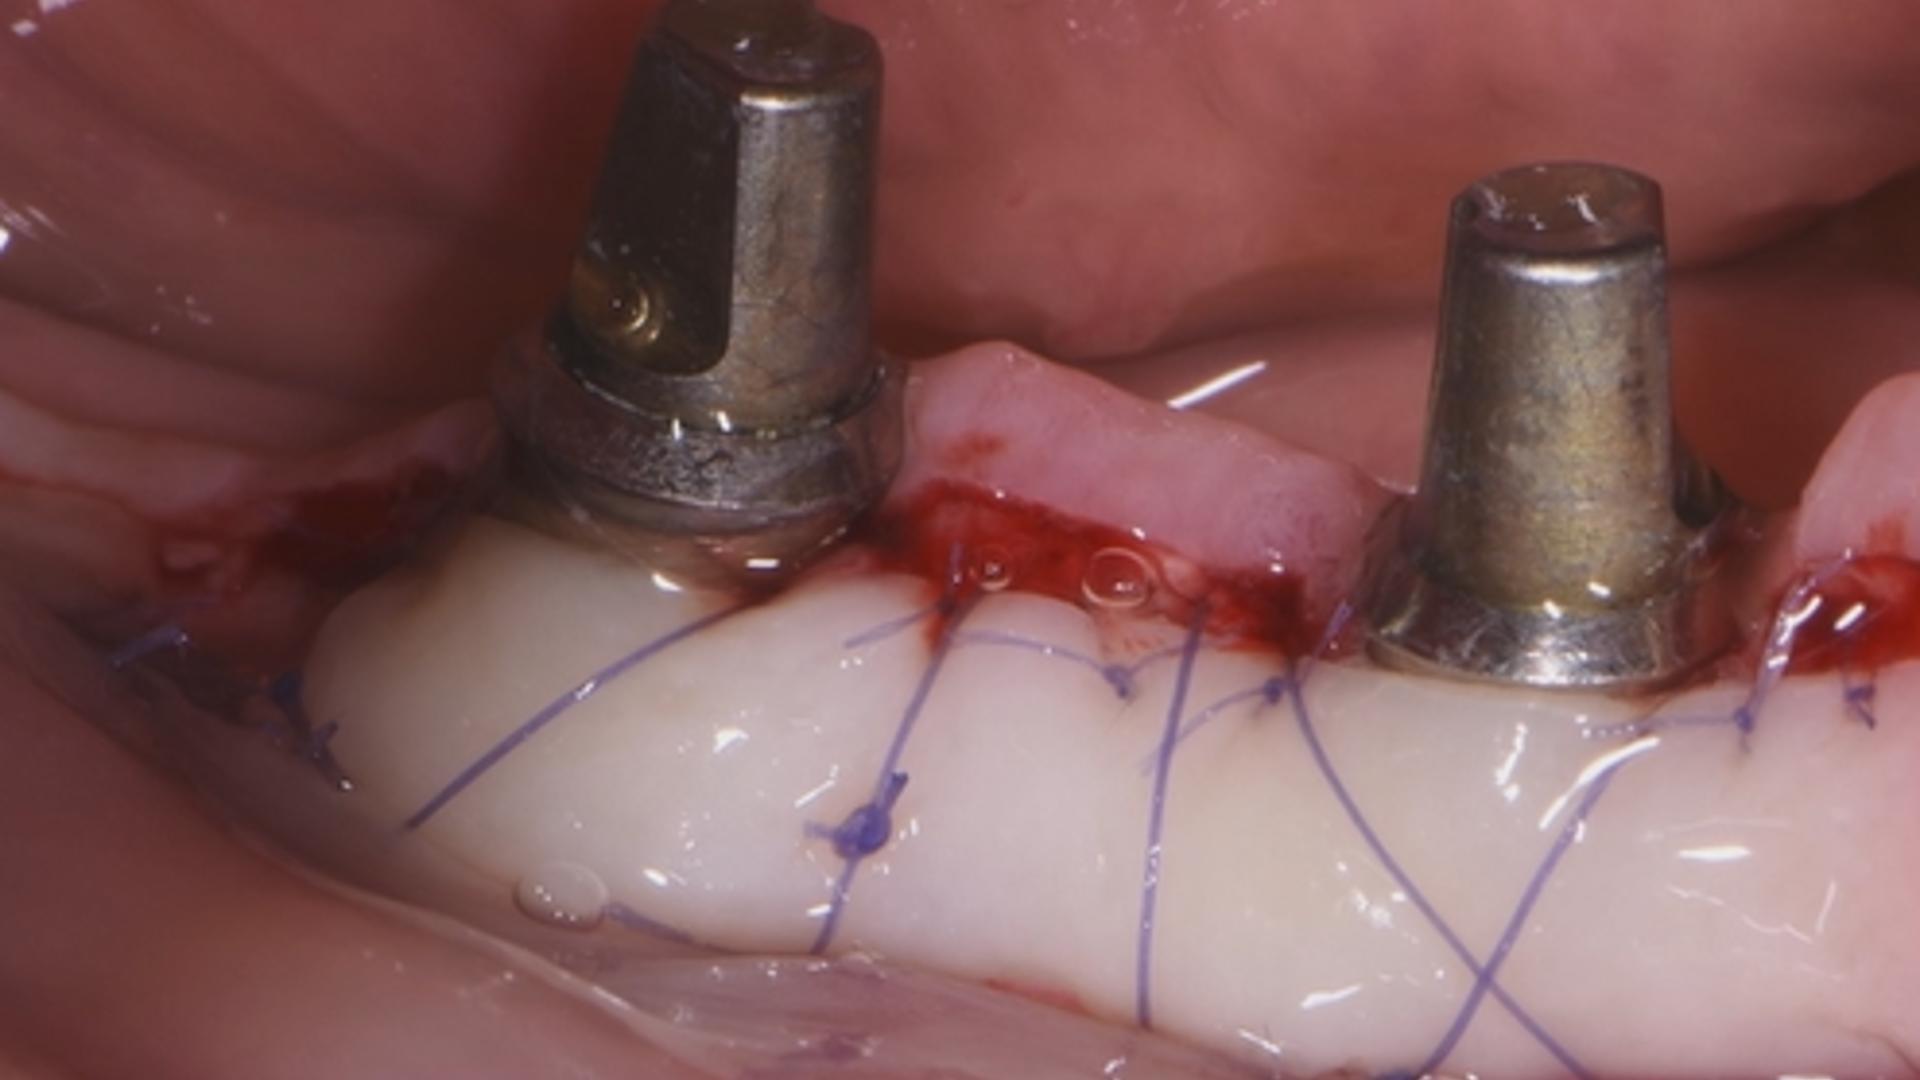

2nd ReLIVE Surgery - Soft tissue augmentation for a guided implant placement at the level of lateral incisor

Hands-On Video Part 3 - Connective tissue graft harvesting and disepithelisation

Hands-On Video Part 4 - Suture protocol